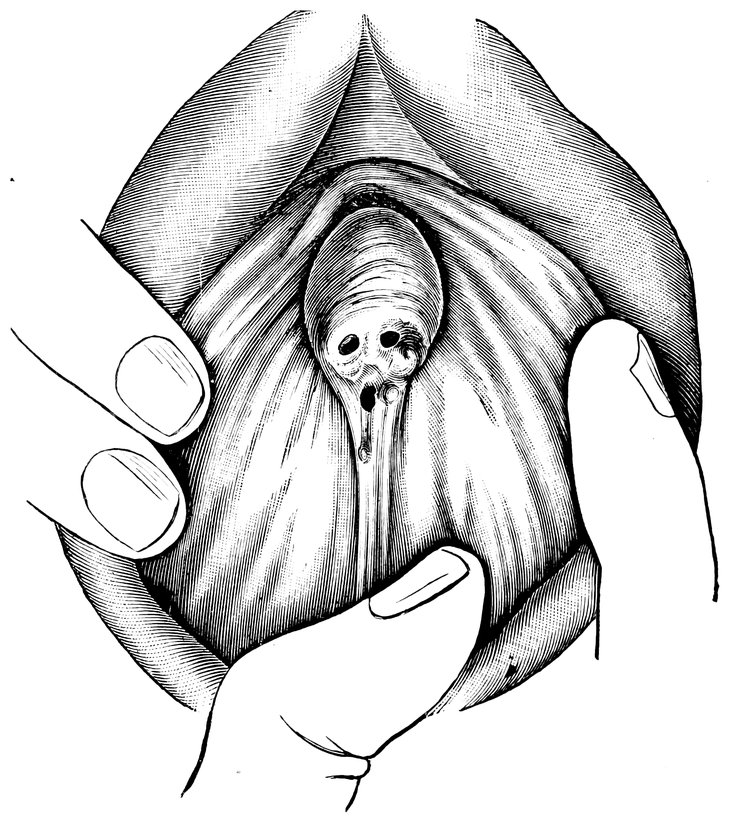

| 44. | Carunculæ Myrtiformes in a Primipara | 71 |

| 45. | Vaginal Inlet of a Multipara, without Carunculæ Myrtiformes. Slight Prolapse of Anterior and Posterior Vaginal Walls | 71 |

| 49. | Vestibule of the vagina, with the labia minora or nymphæ, etc | 205 |